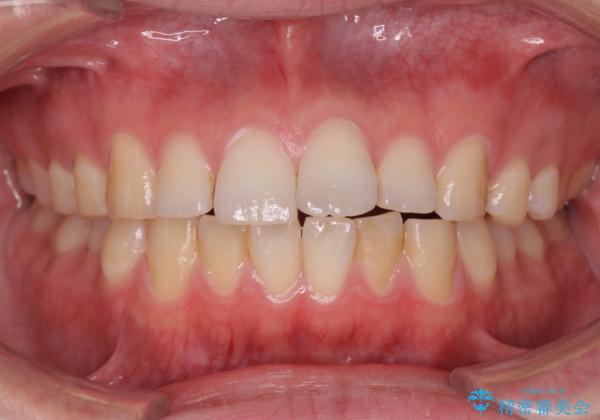

前歯が気になる。インビザラインライト

- 前歯が気になるとの事で来院。

矯正を希望されたが費用と時間を抑えたいとの事でインビザラインライトで矯正を行いました。(奥歯の位置関係はほぼ変えない)

前歯が綺麗に並び大変満足して頂けました。